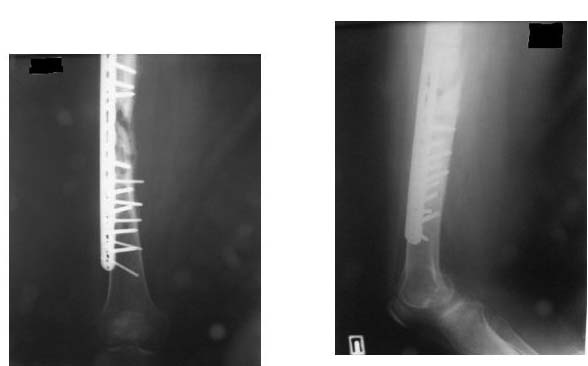

Доброе время суток уважаемые коллеги помогите пожалуйста определиться с тактикой лечения больной. К нам в отделение поступила пациентка с жалобами на боль в области правого бедра, боль возникает при осевой нагрузке на правую н/конечность.

Из анамнеза:  Женщина 41 год травма в июне 2011 в результате ДТП  диагноз: Сочетанная травма - закрытый оскольчатый перелом средней трети правого бедра со смещением отломков.   Оперирована в одной из клиник РФ, произведён  накостный остеосинтез пластиной. П/о период без осложнений, больная была выписана. В декабре 2011 больная поступает в клинику  где была оперирована с диагнозом: Закрытый перелом правого бедра, состояние после остеосинтеза правого бедра, вторичное смещение отломков. Повторно был выполнен остеосинтез правого бедра с аутотрансплантацией. Больная выписана в удовлетворительном состоянии.

С момента последней операции прошло 6 месяцев.

Местно: правое   бедро не деформировано, п/о рубец без признаков воспаления с подлежащими тканями не спаян. Осевая нагрузка болезненна. Движения в тазобедренном и коленном суставе незначительно ограничены.